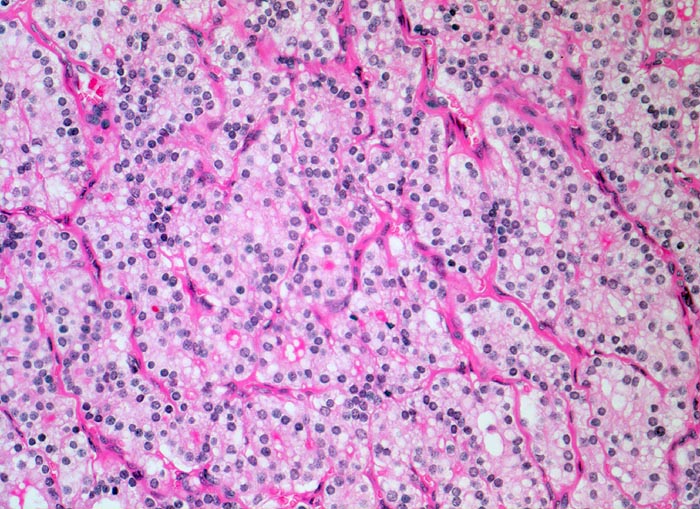

autonomes Adenom

benigner Tumor

Schilddrüse

Die Follikel des endokrin aktiven Adenoms enthalten nur sehr wenig oder gar kein Kolloid. Die Zellen sind kubisch bis hochprismatisch und vielfach mehrreihig angeordnet.

Histologie

200